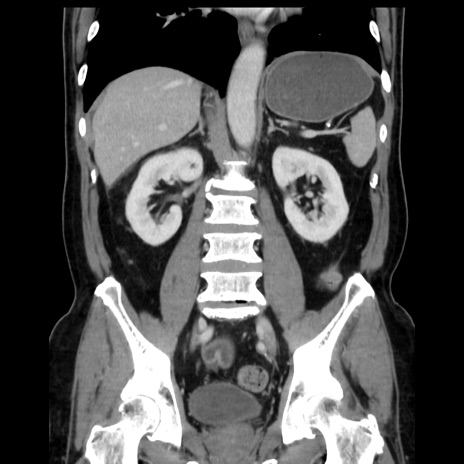

症例16(冠状断像)

【症例】 70歳代男性

【主訴】 腹痛、嘔吐

【現病歴】 約1ヶ月前より間欠的に腹痛と嘔吐あり、当院消化器内科を受診したところCTで多発する肝臓のLDAを指摘され、精査中であった。以降は消化器症状は安定していたが、2日前より嘔気と腹痛があり、同日より排便・排ガスが消失した。改善認めず、 本日、救急外来を受診した。

【既往歴】 大腸ポリープ切除後。

【身体所見】意識清明・会話良好、BT 36.3℃、BP 127/80mmHg、 P 80bpm、腹部:膨満あり、平坦・軟、上腹部正中および下腹部正中に圧痛あり、反跳痛なし、筋性防御なし。

【データ】WBC 7200、CRP 0.77